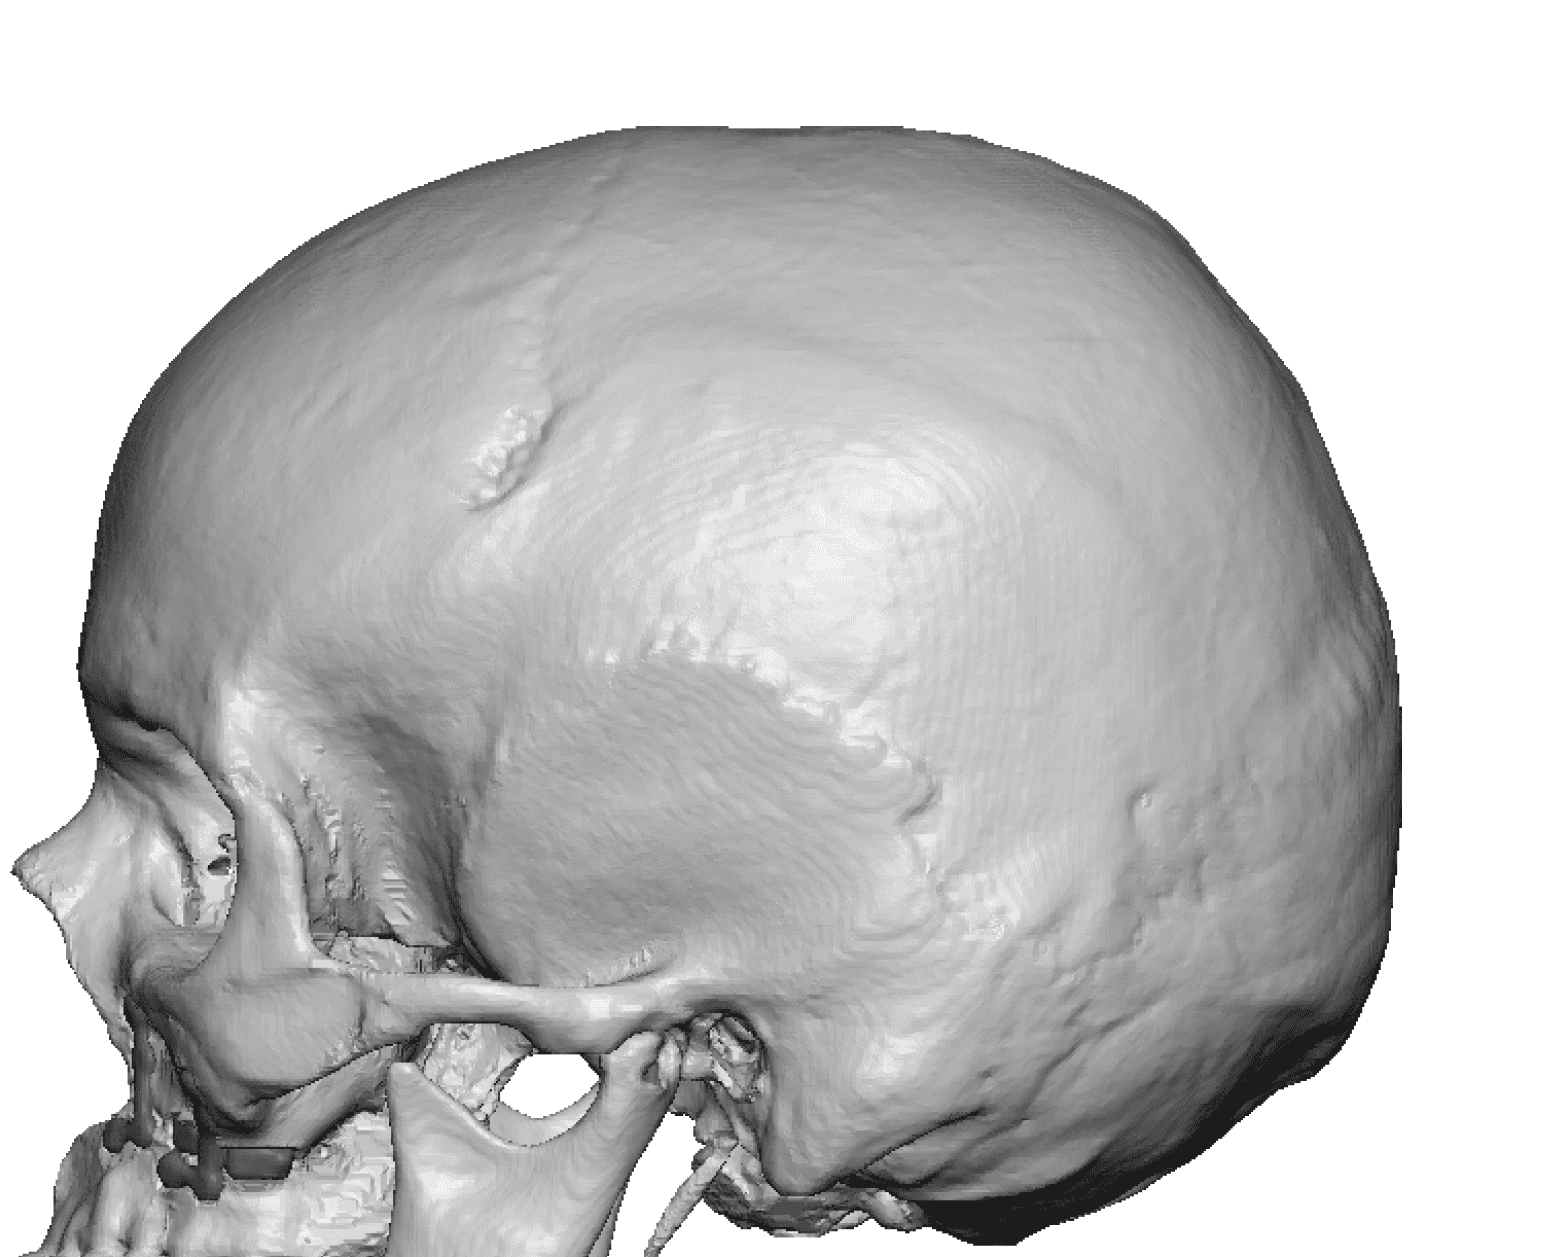

Severe narrowing skull deformity from prior sagittal craniosynostosis repair as an adult.

Complete replacement of entire skull by a custom implant with temporal fat injections.

Severe narrowing skull deformity from prior sagittal craniosynostosis repair as an adult.

Complete replacement of entire skull by a custom implant with temporal fat injections.